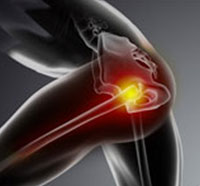

The hip joint is a "ball and socket" joint. The "ball" is the head of the femur or thigh bone, and the "socket" is the cup-shaped acetabulum. The joint surface is covered by a smooth articular surface that allows pain-free movement in the joint.

The hip joint is one of the largest weight-bearing joints in the body, formed by the thigh bone or femur and the acetabulum of the pelvis. It is a ball and socket joint with the head of the femur as the ball and the pelvic acetabulum forming the socket.

The hip joint is one of the body's largest weight-bearing joints and is the point where the thigh bone (femur) and the pelvis (acetabulum) join. It is a ball and socket joint in which the head of the femur is the ball and the pelvic acetabulum forms the socket.